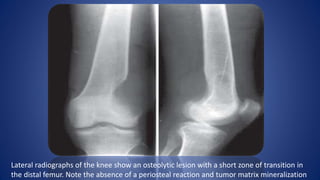

Lateral radiographs of the knee show an osteolytic lesion with a short zone of transition in

the distal femur. Note the absence of a periosteal reaction and tumor matrix mineralization